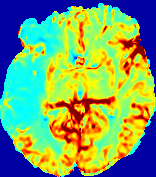

4.3.2 Diffusion Imaging via Advection-Diffusion

Slice #1Slice #2Slice #3Slice #4Slice #5Slice #6Dgtsuperscript𝐷gtD^{\text{gt}}Refer to captionRefer to captionRefer to captionRefer to captionRefer to captionRefer to captionDestsuperscript𝐷estD^{\text{est}}Refer to captionRefer to captionRefer to captionRefer to captionRefer to captionRefer to captionRefer to caption0.300.300.300.240.240.240.180.180.180.120.120.120.060.060.060.000.000.00(mm2/s)𝑚superscript𝑚2𝑠(mm^{2}/s)𝐕est𝟐subscriptnormsuperscript𝐕est2\|\bf{V}^{\text{est}}\|_{2}Refer to captionRefer to captionRefer to captionRefer to captionRefer to captionRefer to captionRefer to caption0.00300.00300.00300.00240.00240.00240.00180.00180.00180.00120.00120.00120.00060.00060.00060.00000.00000.0000(mm/s)𝑚𝑚𝑠(mm/s)

Figure 15: PIANO identifiability testing: diffusion imaging via advection-diffusion. Top row shows Dgtsuperscript𝐷gtD^{\text{gt}} used for simulating ground truth pure diffusion. Rows below show the estimated Destsuperscript𝐷estD^{\text{est}} and 𝐕est2subscriptnormsuperscript𝐕est2\|{\bf{V}}^{\text{est}}\|_{2} on corresponding slices. Note that the plotted value scale for 𝐕est2subscriptnormsuperscript𝐕est2\|{\bf{V}}^{\text{est}}\|_{2} is 0.01 of that for Dgtsuperscript𝐷gtD^{\text{gt}} and Destsuperscript𝐷estD^{\text{est}}.

Similarly, we test the behavior of PIANO when estimating both advection and diffusion from a pure diffusion-driven process. The goal is to determine if PIANO is able to recognize that there is only diffusion governing the given concentration time-series. We use the same ‘Diffusion Imaging’ data simulation of Sec. 4.2.1 as the concentration dataset, PIANO estimates both velocity 𝐕estsuperscript𝐕est{\bf{V}}^{\text{est}} and diffusivity Destsuperscript𝐷estD^{\text{est}}. Estimation results in Fig. 15 confirm PIANO’s identifiability again: the estimated 𝐕est2subscriptnormsuperscript𝐕est2\|{\bf{V}}^{\text{est}}\|_{2} is almost invisible compared to Destsuperscript𝐷estD^{\text{est}}, even plotted with a 1%percent11\% value range compared to that for Destsuperscript𝐷estD^{\text{est}}. On the other hand, Destsuperscript𝐷estD^{\text{est}} achieves comparable estimation performance as ‘Diffusion Imaging via Diffusion’ in which PIANO predicts Destsuperscript𝐷estD^{\text{est}} alone (shown in Fig. 13).